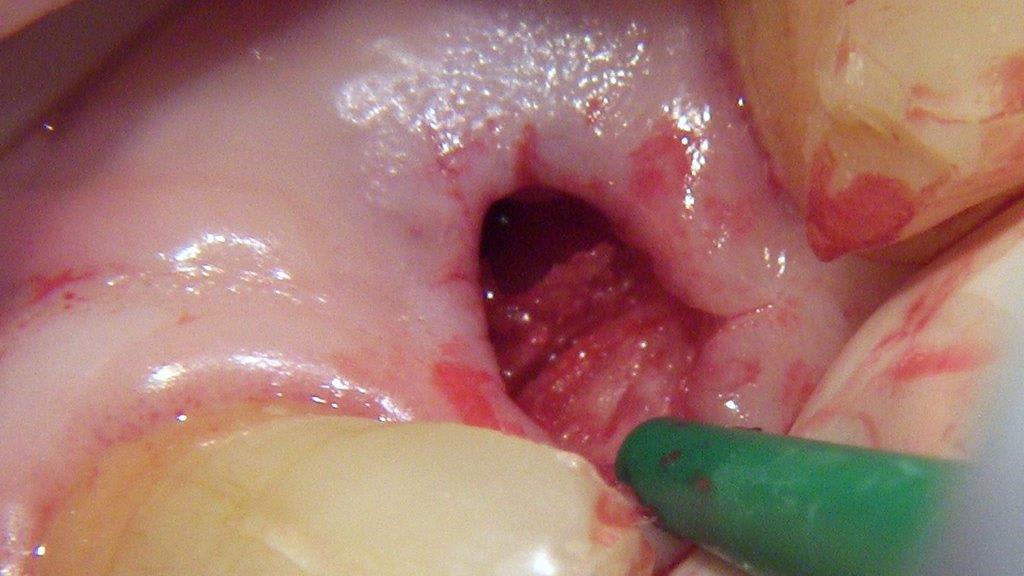

pour ceux que ça intéressent, une petite utilisation d'expansion de la paroi palatine, sur une avulsion d’incisive(racine fendue). toutes mes excuses pour la mauvaise qualité des photos.